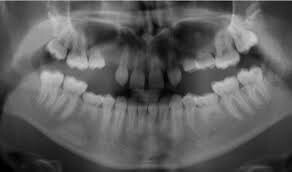

Your dental professional will be able to tell if you have any missing teeth. Usually, they will need an x-ray to confirm this. Gaps between your teeth, losing a baby tooth with no adult tooth taking its place or having a baby tooth longer than normal are all signs of having congenitally missing teeth.

In the case of having no adult tooth to replace a baby tooth, sometimes the baby tooth remains in the mouth longer than it is meant to. There are cases where they can last well into adulthood, depending on the condition of the tooth and how long the roots are. At some point, the baby tooth may need to be extracted, and it is a good idea to have a treatment plan ready for how to fill the space.